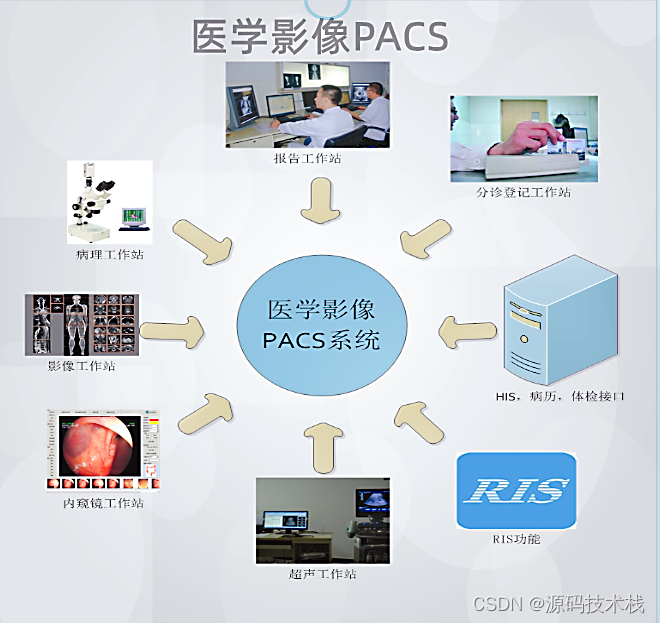

PACS是Picture Archiving and Communication Systems首字母缩写,全称为影像储存和传输系统,涉及放射医学、计算机技术、通讯技术及数字图像技术等,是医院信息系统的重要组成部分,是将数字医疗设备(如X线、CT、MRI、超声、病理等)所产生的医疗图像进行获取、储存、管理、诊断及信息处理的重要系统。PACS集医疗图像获取、数据储存、图像的显示和处理、数据管理及传输影像等技术为一体,大大降低了医生对传统硬拷贝技术的依赖。

PACS主要包括图像获取、图像传输、图像储存和管理、图像影像工作站进行阅读四个流程。临床上,PACS系统流程从患者在登记台登记检查开始,然后患者进入检查室,技师进行检查,采集影像数据,将采集的影像数据进行上传至PACS网,影像医师通过PACS调阅图像并书写报告,最后将PACS的图文报告归档。